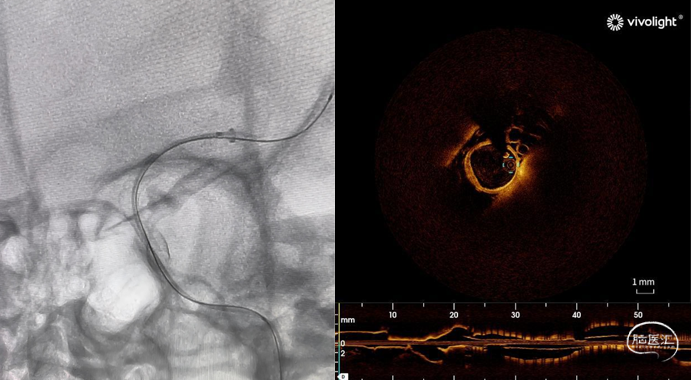

微光自研携手INT璞霖医疗,全球首款神经介入OCT(光学相干断层成像)导管LumenCross® F2正式上市!这一革命性产品的问世,标志着神经介入领域技术的重大突破,也为广大患者带来了更加精准、安全的治疗方案。

此款OCT导管专为神经介手术设计(适用于颈动脉),具有大范围成像、高清分辨、高顺应性和卓越通过性的独特优势,将为医生提供更全面、更精准的手术支持,开启神经介入手术的精准化治疗新时代。